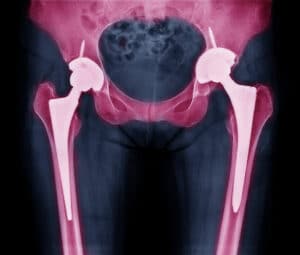

Staying active is important for many adults who enjoy sports, fitness, and living a full life. When hip pain from arthritis or injury makes movement difficult, it can feel frustrating and discouraging. Many adults worry that hip replacement will make them slow down or stop doing their favorite activities. However, new advances in surgery and prosthetic design can help restore movement. Let us explore the options for the best hip replacement for an active person. We will also discuss [Read More]

Best Hip Replacement: A Guide for Active Adults

Staying active is important for your health and happiness, but hip pain can make even small movements hard. Hip pain can happen because of aging, arthritis, or an injury, and it can stop you from staying active. For adults who want to keep moving and stay independent, hip replacement surgery can be a life-changing option. This article will explain the best hip replacement options for an active person and how to make good decisions for your care. Choosing the Best Hip Replacement [Read More]